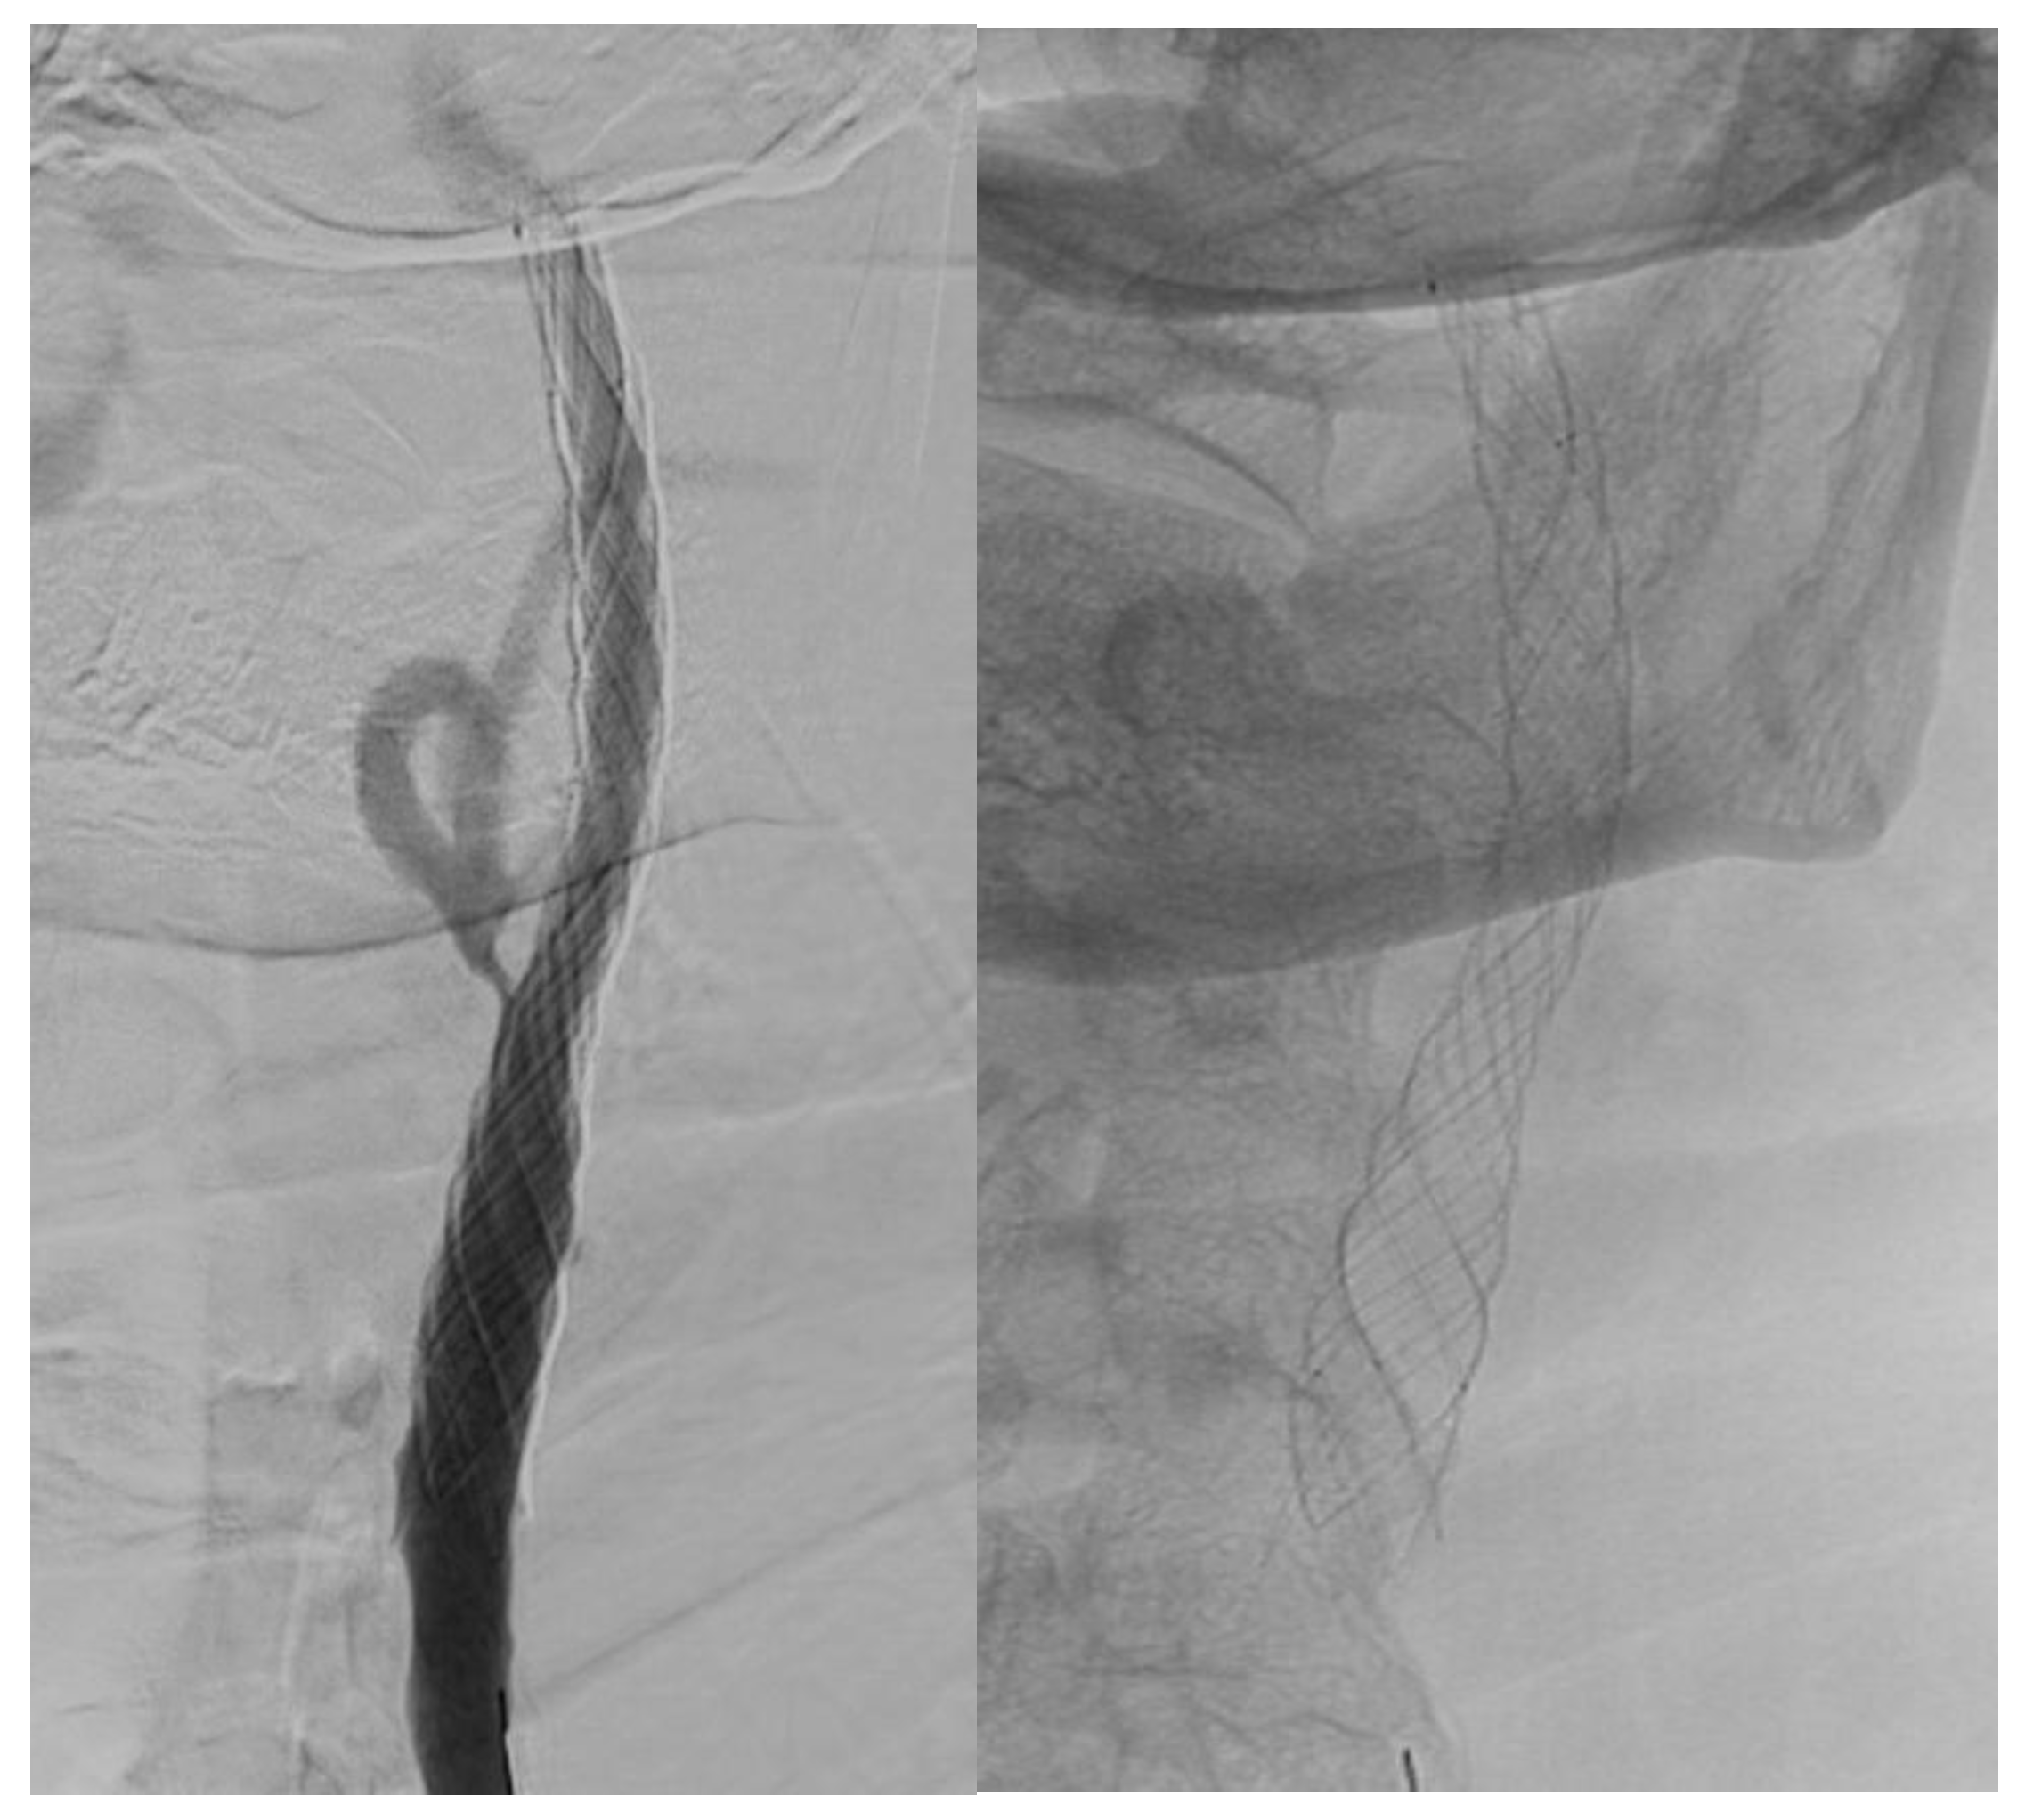

After 2015, there was an increased usage of new types of double-layer carotid stents: Roadsaver™ Carotid Artery Stent (Terumo Interventional Systems) 23.0% (n = 132) and CGuard carotid stent system (Inspire MD, Boston, MA, USA) 3.1% (n = 18) (Table 7).

Visual differences between single- and double-layer carotid stents as seen during the angiography procedure are illustrated in Figure 2, Figure 3 and Figure 4.

Figure 3. Double-layer micromesh stent (Cguard-Inspire MD).

Jcm 14 00888 g003